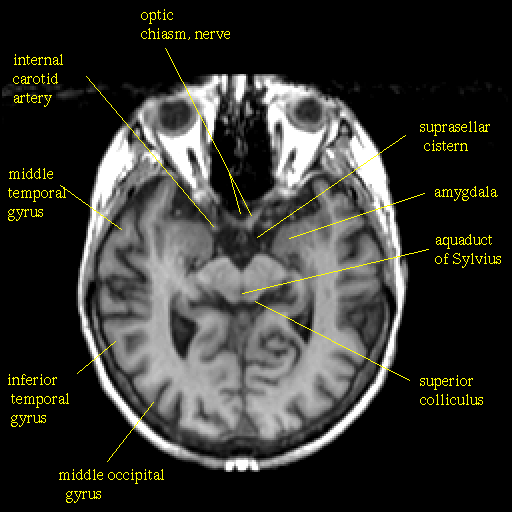

T1-weighted structural MR: Slice 23

Slice 23